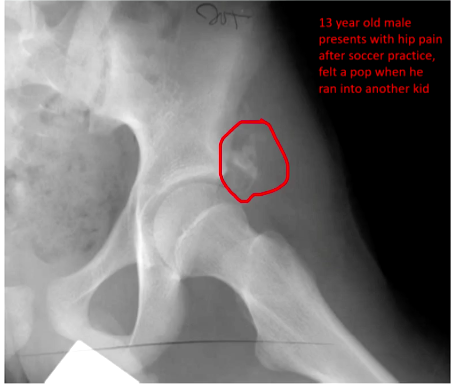

Evulsion (?) fracture at the ASIS would injure what msucle?

One of the heads of the rectus femoris.

Evulsion fracture at the ischium would injure what muscle?

Hamstrings